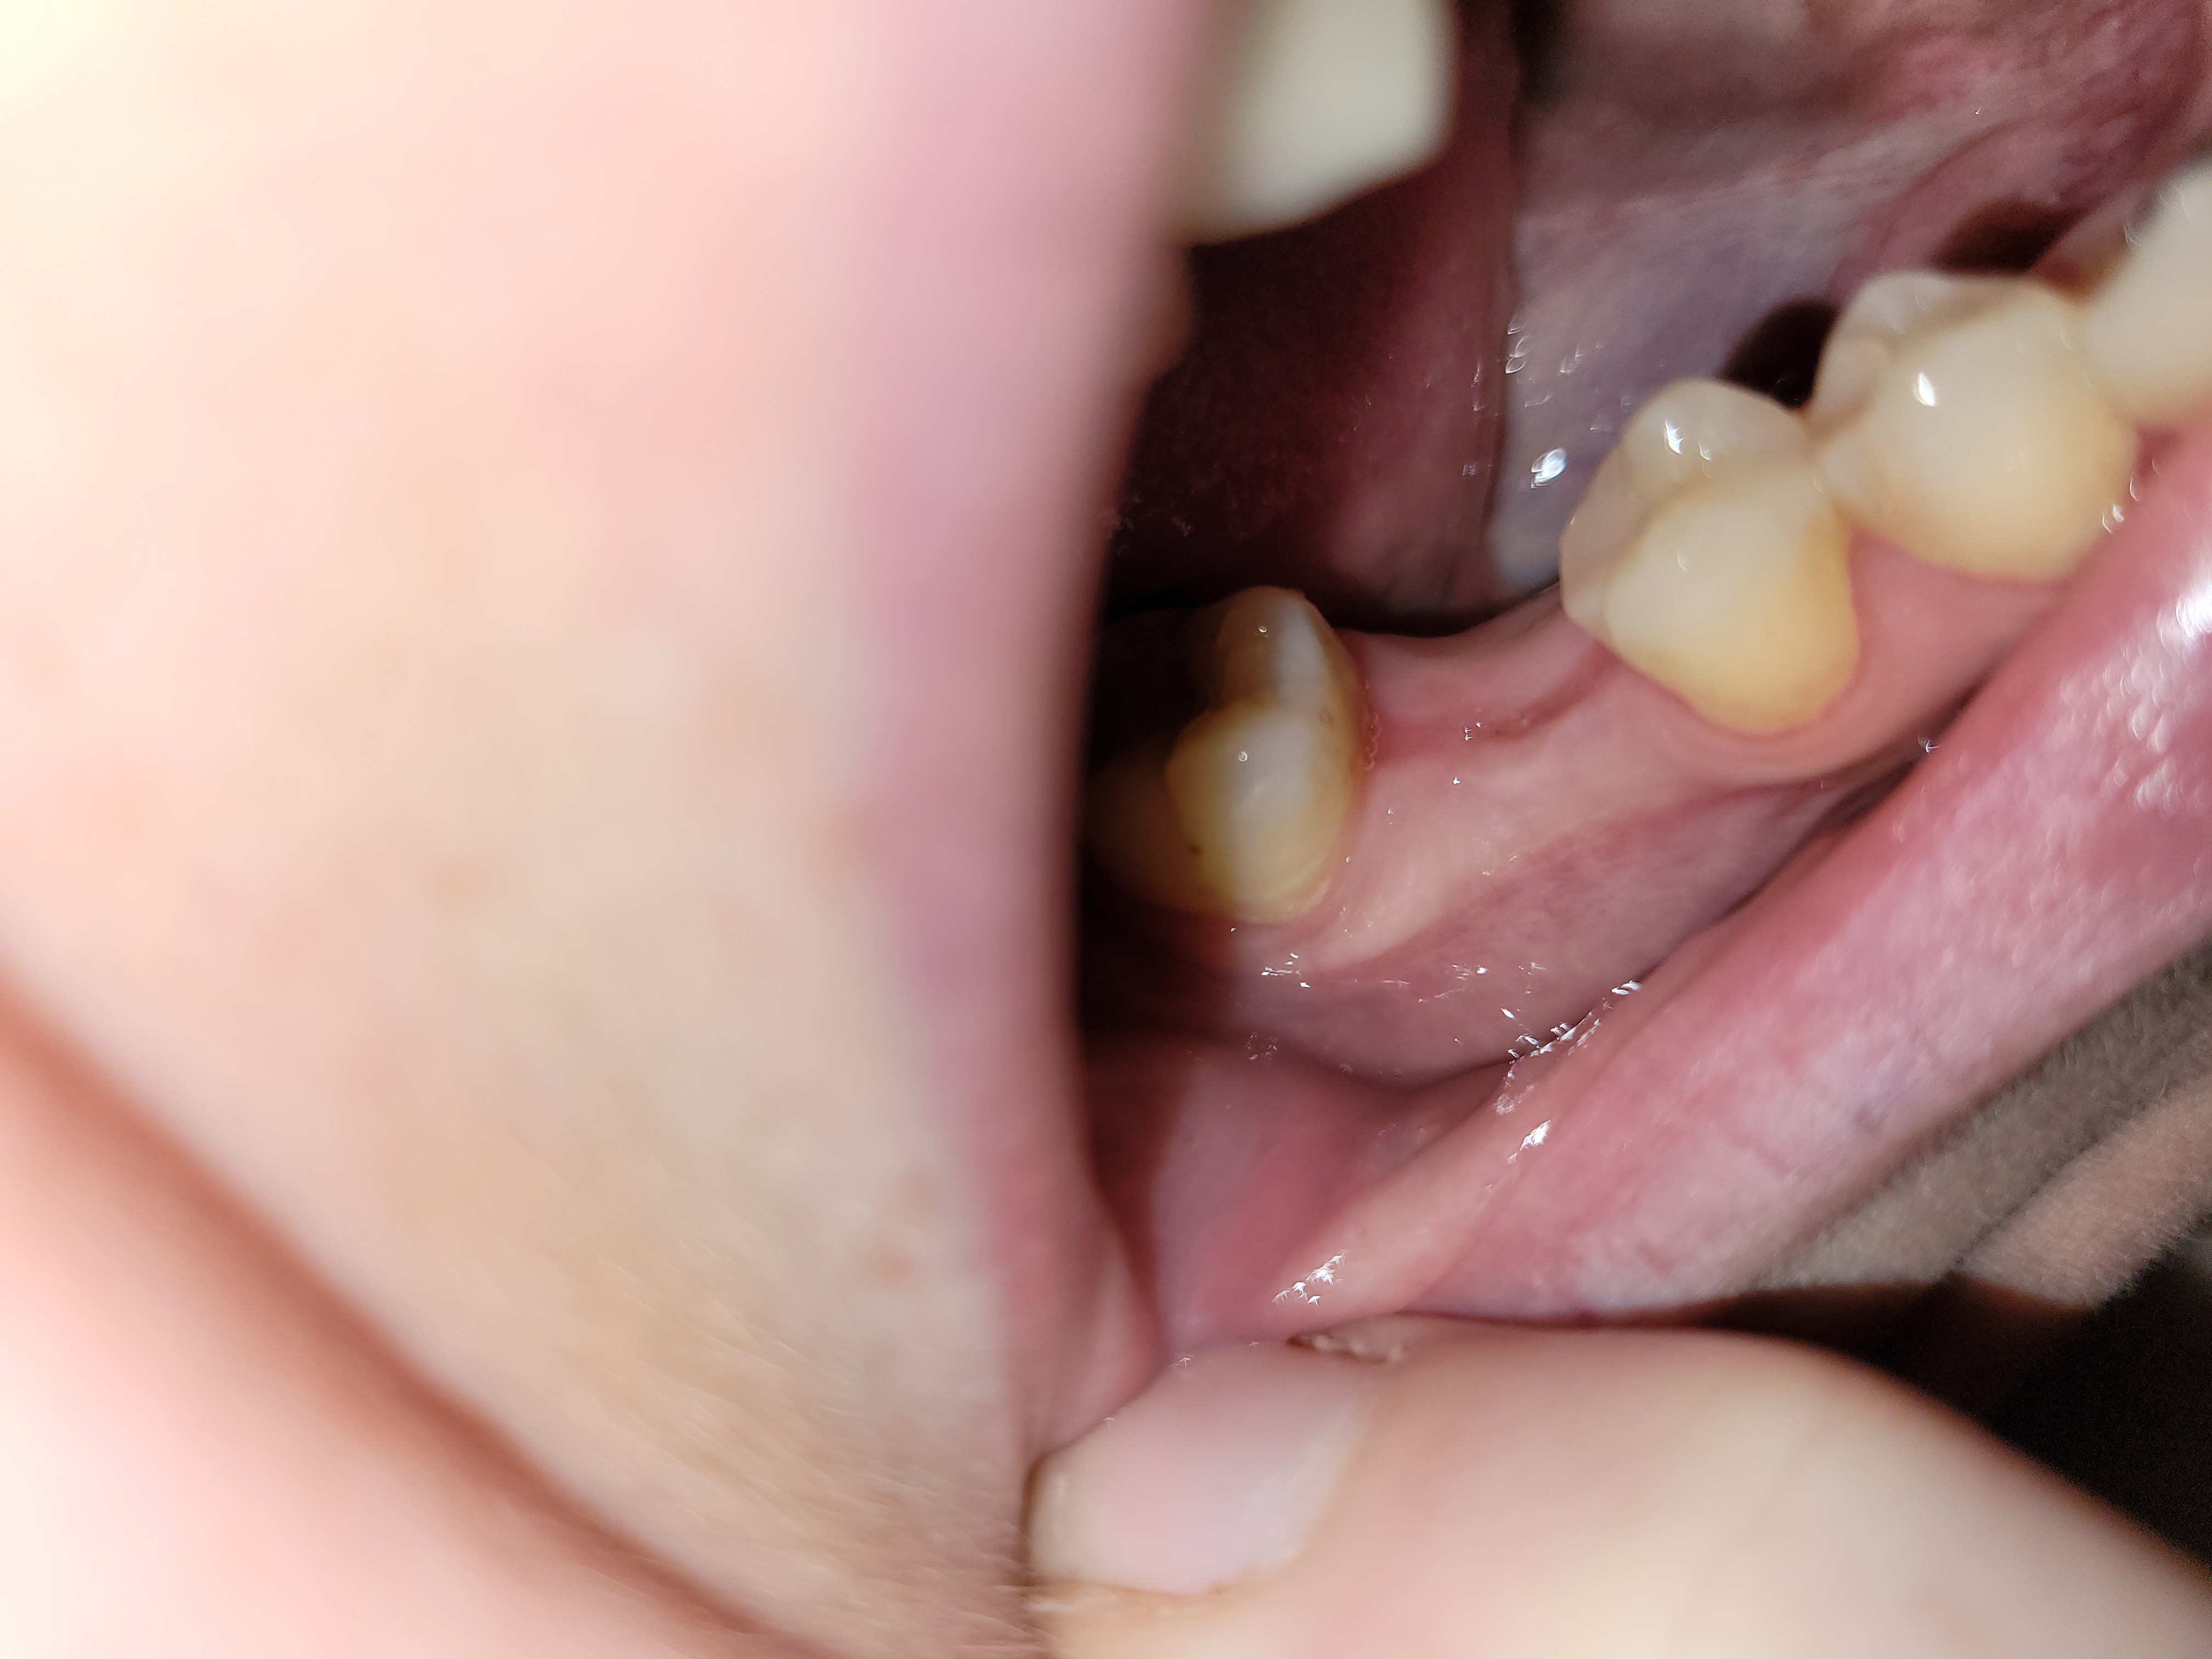

Vielen Dank für Ihre Antwort. So sieht es heute, 3 monate nach EX aus. Passt das so? Der kleine punkt in der Mulde ist immer wieder mal sichtbar (mal rot, mal weiß). Sollte es eine Fistel sein, gibt sich das von alleine? Kann sich da jetzt noch was entzünden?

wunde sieht gut aus.

kann sein dass noch in der tiefe das ganze heilt, deswegen der punkt. sollte aber immer weniger werden!